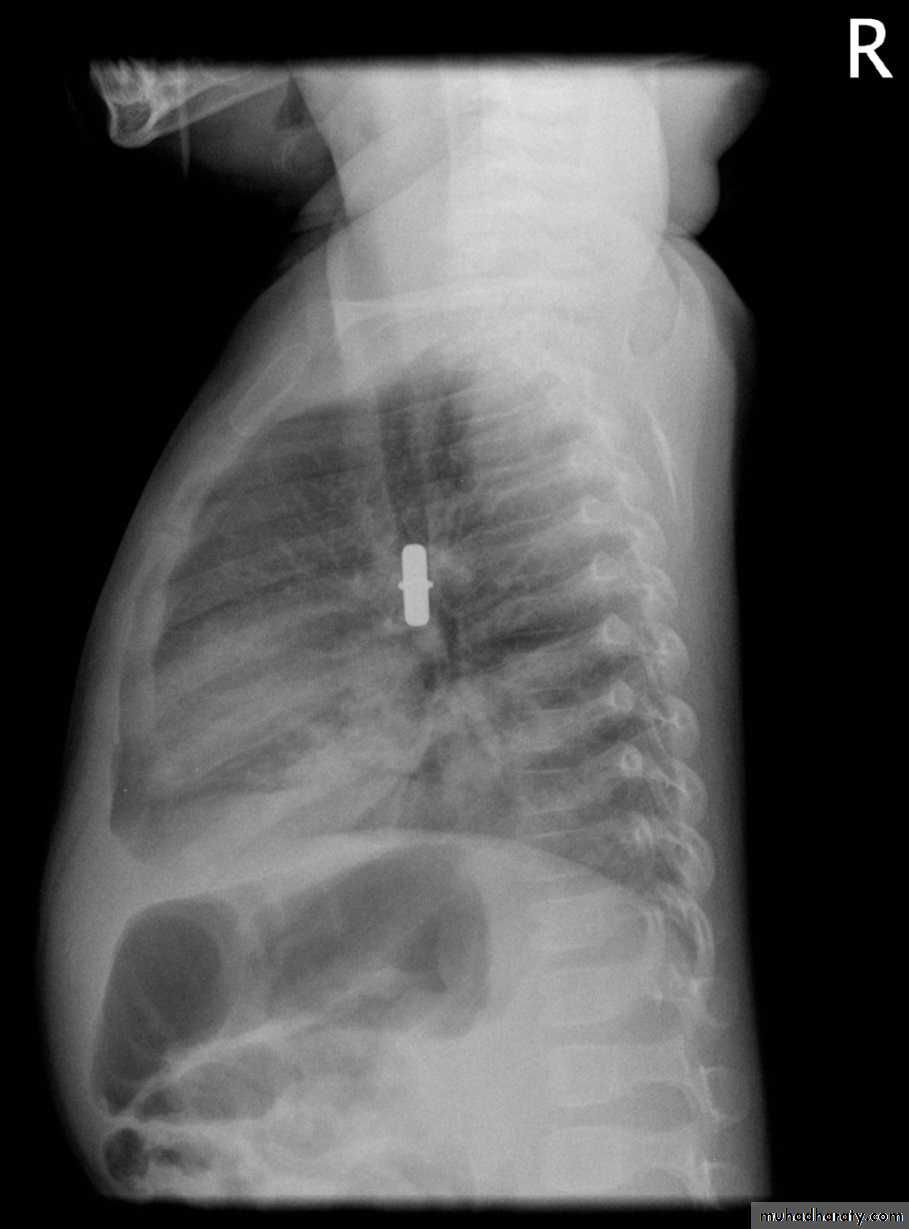

Foreign Body Inhalation

A common problem

Most common site for foreign body inhalation is?Clinical presentation:

• Asymptomatic only discovered by a witness• Stridor with dyspnea if stuck in the trachea or larynx

• wheezing with a persistent cough when in the bronchus

• repeated or persistent pneumonia with suppuration (late presentation).

Investigations:

Chest X-ray:

DDx: FB in the esophagus